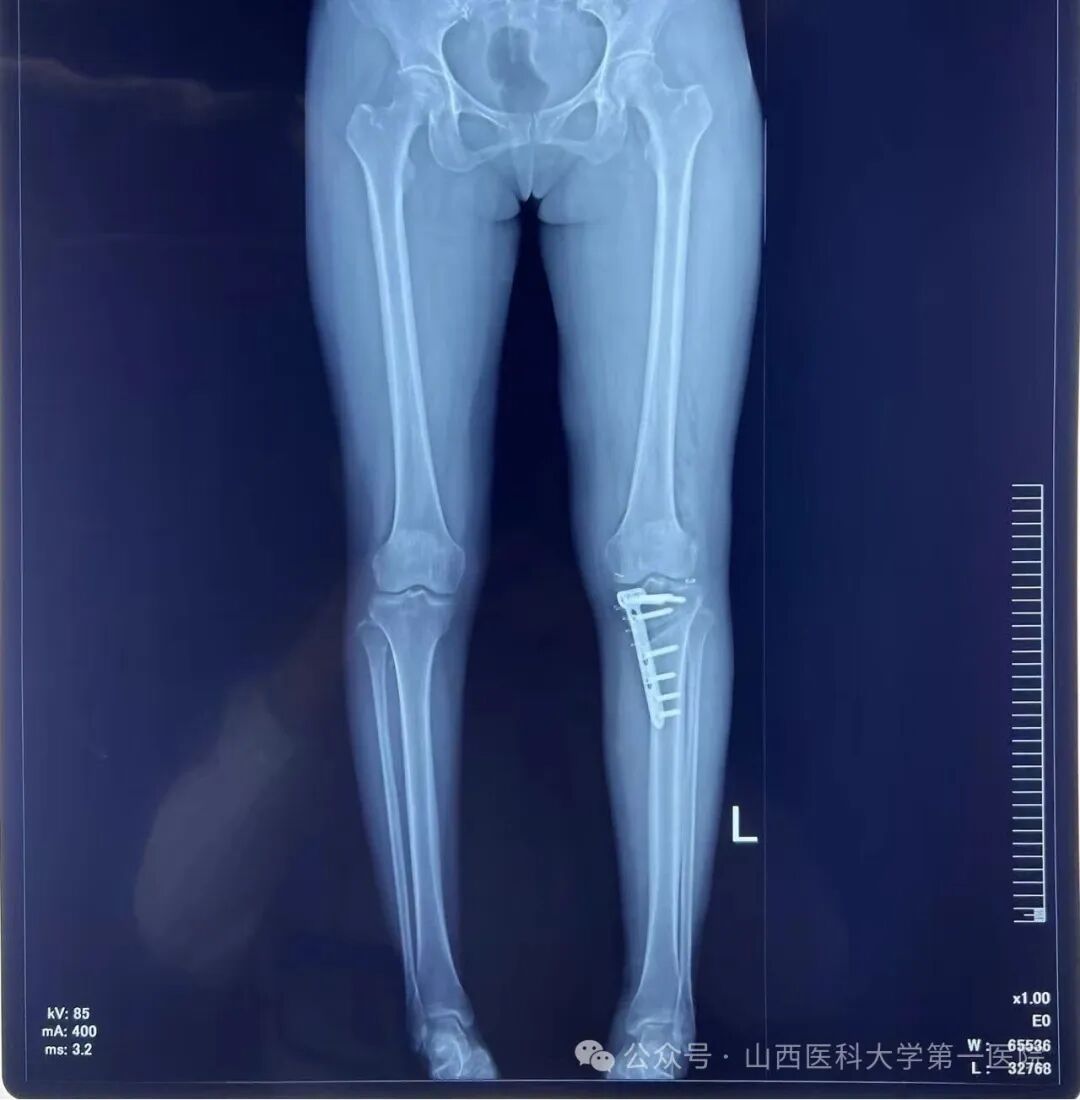

术后左下肢力线明显矫正

此次手术患者的膝关节核磁显示半月板有明显的撕裂,因此单纯行HTO无法解决半月板损伤的问题。骨科主任杨自权作为山西省运动医学的领军人物,运用关节镜为患者解决半月板损伤的问题,同时在AI设计的3D-PSI的辅助下实施精确地截骨矫正下肢机械轴力线,从而达到令人满意的手术效果。

数字化3D-PSI在HTO的应用已在全世界范围获得认可,对于患者来说,定制化的导板匹配性高,可以减少手术出血量和X线透视次数;对于医生来说,不仅能简化手术步骤、缩短手术时间,还能提高手术精准度和降低手术风险,为此,杨自权主任团队坚持走在数字化骨科的第一线,从今年初完成大量机器人辅助下的全髋关节、全膝关节置换到今天的AI智能3D-PSI截骨挡板辅助下的保膝手术,使山医大一院骨科始终站在国内乃至国际医学前沿,全面进入数智骨科时代,有能力运用微创、AI智能工具等先进技术为群众健康保驾护航,并推动山西省关节外科和骨外科学向智能化迈进。